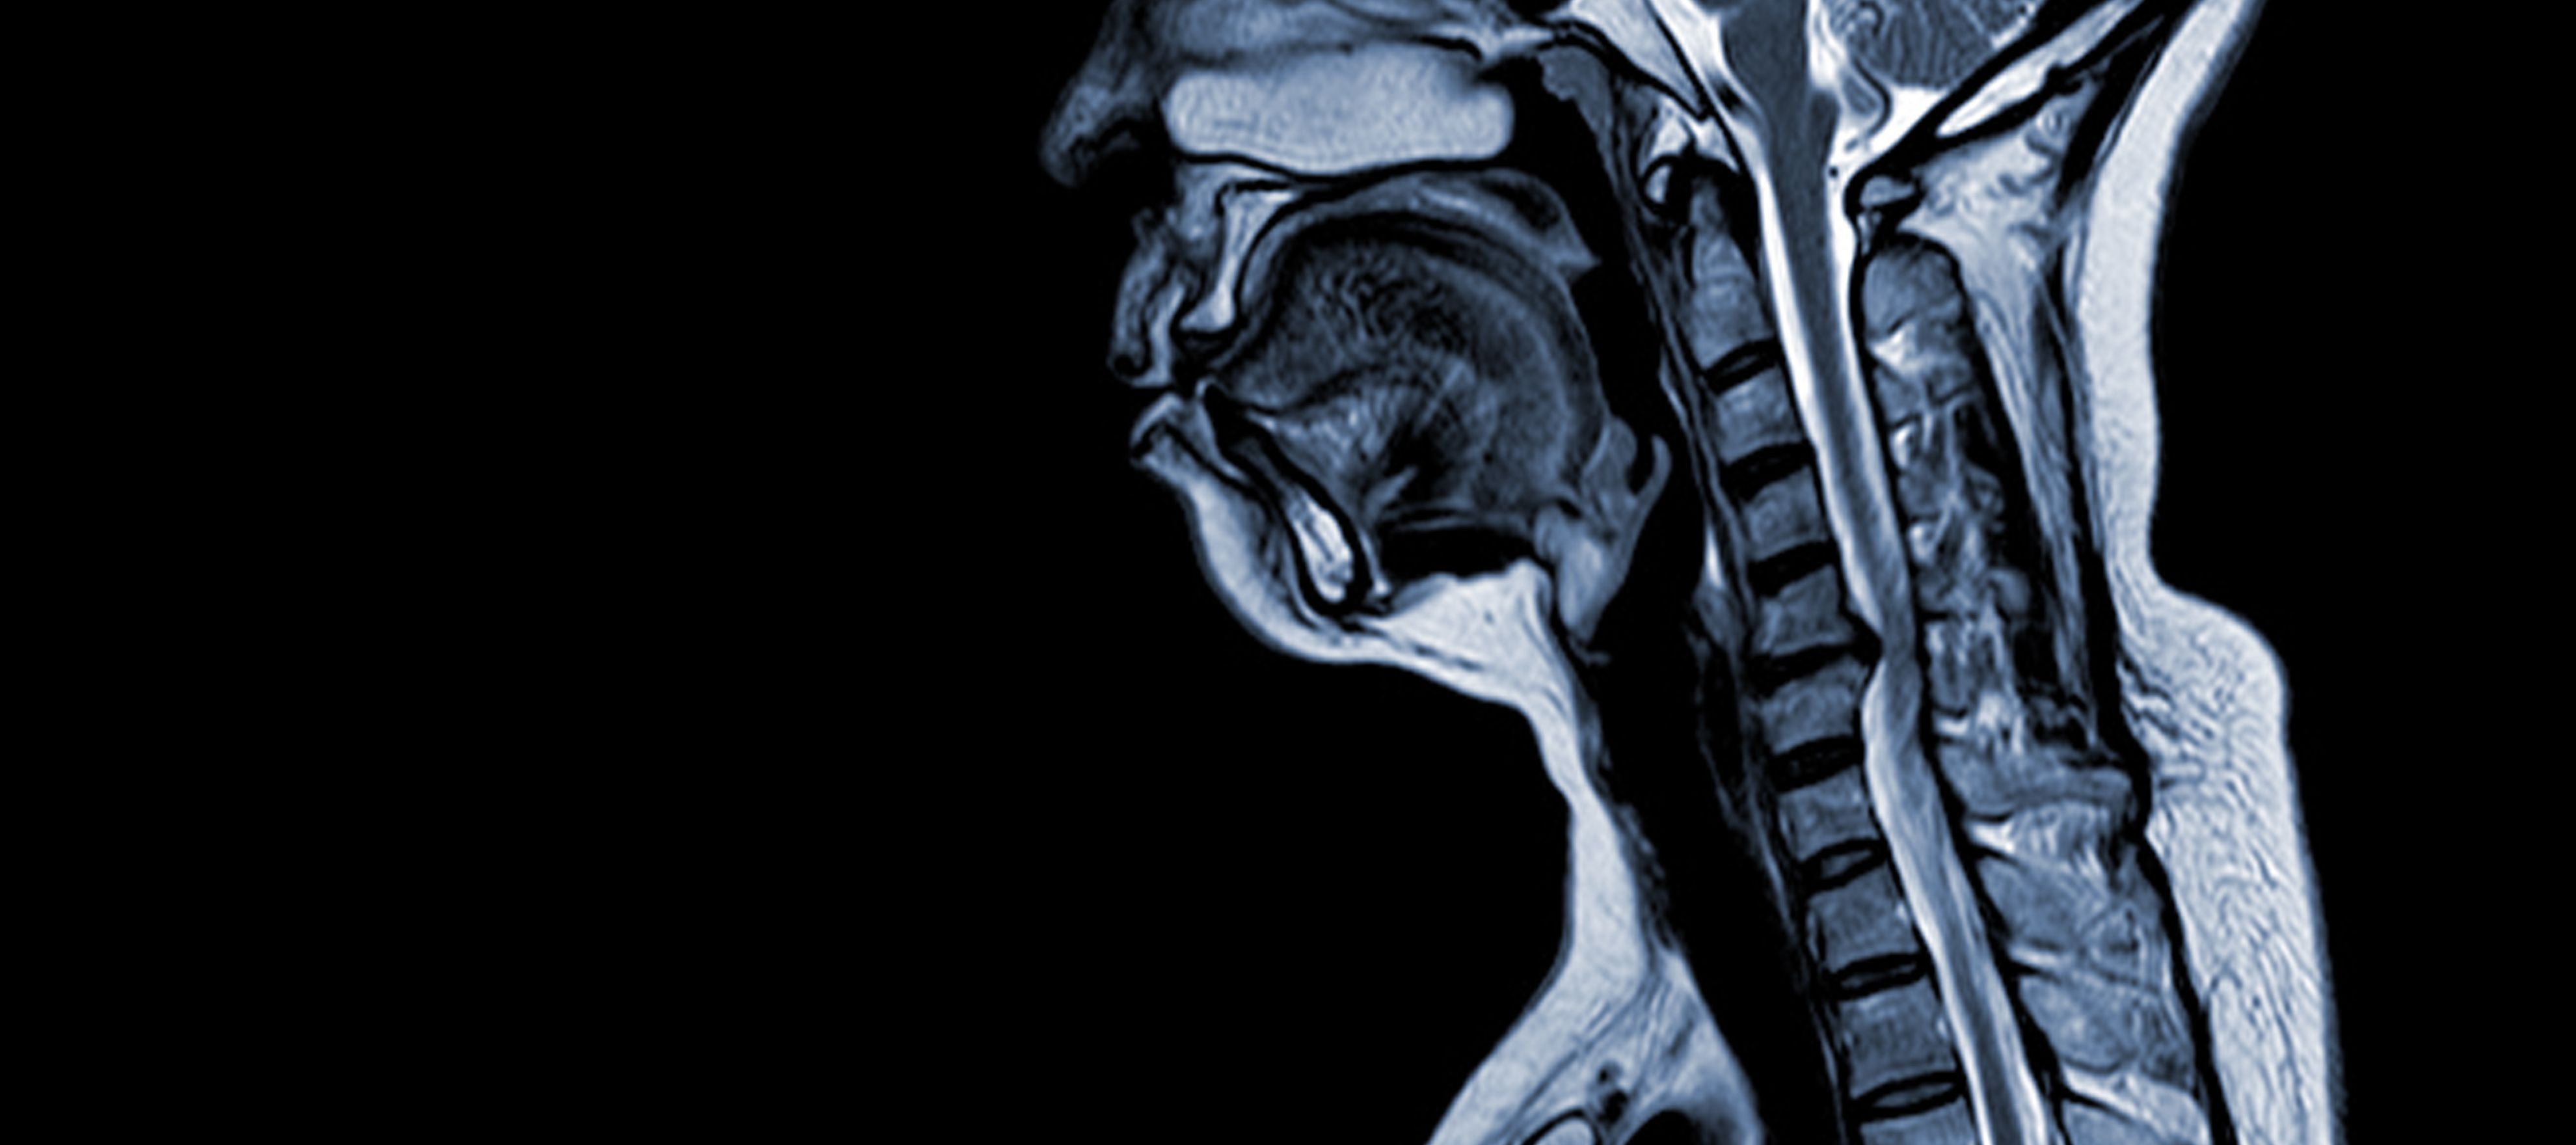

Die zervikale spondylotische Myelopathie (CSM) ist eine neurologische Erkrankung, die die häufigste Ursache für Rückenmarksverletzungen bei Erwachsenen darstellt. Vereinfacht ausgedrückt handelt es sich um eine Kompression oder Schädigung des Rückenmarks im Nackenbereich, die in erster Linie auf den natürlichen Alterungsprozess zurückzuführen ist, der die Halswirbel betrifft. Der Begriff "Myelopathie" leitet sich von den griechischen Wörtern "myelon", was "Rückenmark" bedeutet, und "pathos", was "Krankheit" bedeutet, ab.

Pathophysiologie

- Bandscheibendegeneration (Bulging Disc): CSM beginnt häufig mit der Degeneration von Bandscheiben in der Halswirbelsäule, die sich vorwölben oder in den Wirbelkanal vorstehen.

- Subperiostale Knochenbildung (ventral des Spinalkanals): Als Reaktion auf die erhöhte mechanische Belastung bildet der Körper neues Knochengewebe an der vorderen (ventralen) Seite des Wirbelkanals, wodurch der Raum für das Rückenmark verengt werden kann.

- Verknöcherung des hinteren Längsbandes: Das hintere Längsband kann verknöchern, verhärten und verkalken und so zur Verengung des Wirbelkanals beitragen.

- Hypertrophie des Ligamentum Flavum: Eine Hypertrophie des Ligamentum Flavum führt dazu, dass es sich verdickt und weniger flexibel wird, wodurch der Raum im Wirbelkanal weiter eingeengt und das Rückenmark zusammengedrückt wird.

Diese strukturellen Veränderungen führen insgesamt zu einer Kompression und Verengung des Wirbelkanals, was zu den charakteristischen Symptomen und Komplikationen der CSM führt. Das Erkennen dieser Risikofaktoren und das Verständnis der beteiligten pathophysiologischen Mechanismen ist sowohl für die Prävention als auch für die Behandlung von wesentlicher Bedeutung. Eine frühzeitige Diagnose und geeignete Maßnahmen sind entscheidend, um die Auswirkungen dieser strukturellen Veränderungen auf das Rückenmark abzumildern.